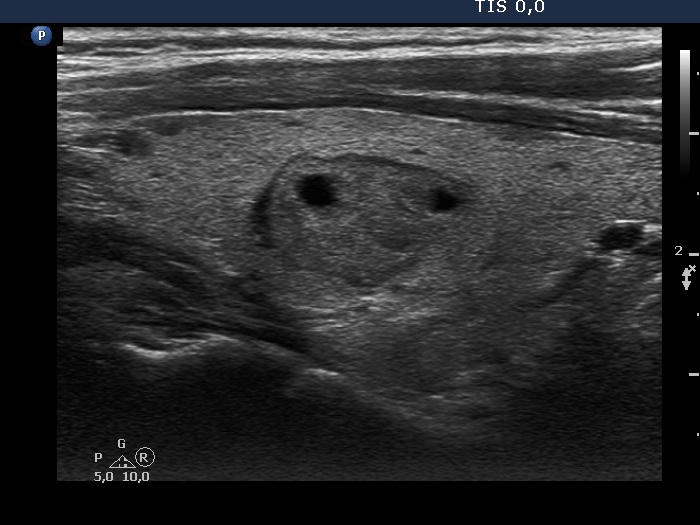

Study on 100 consecutive patients with thyroid nodule - case 038 (ultrasonographic picture 2)

Right lobe, longitudinal scan. The nodule has halo and contains small cystic areas.